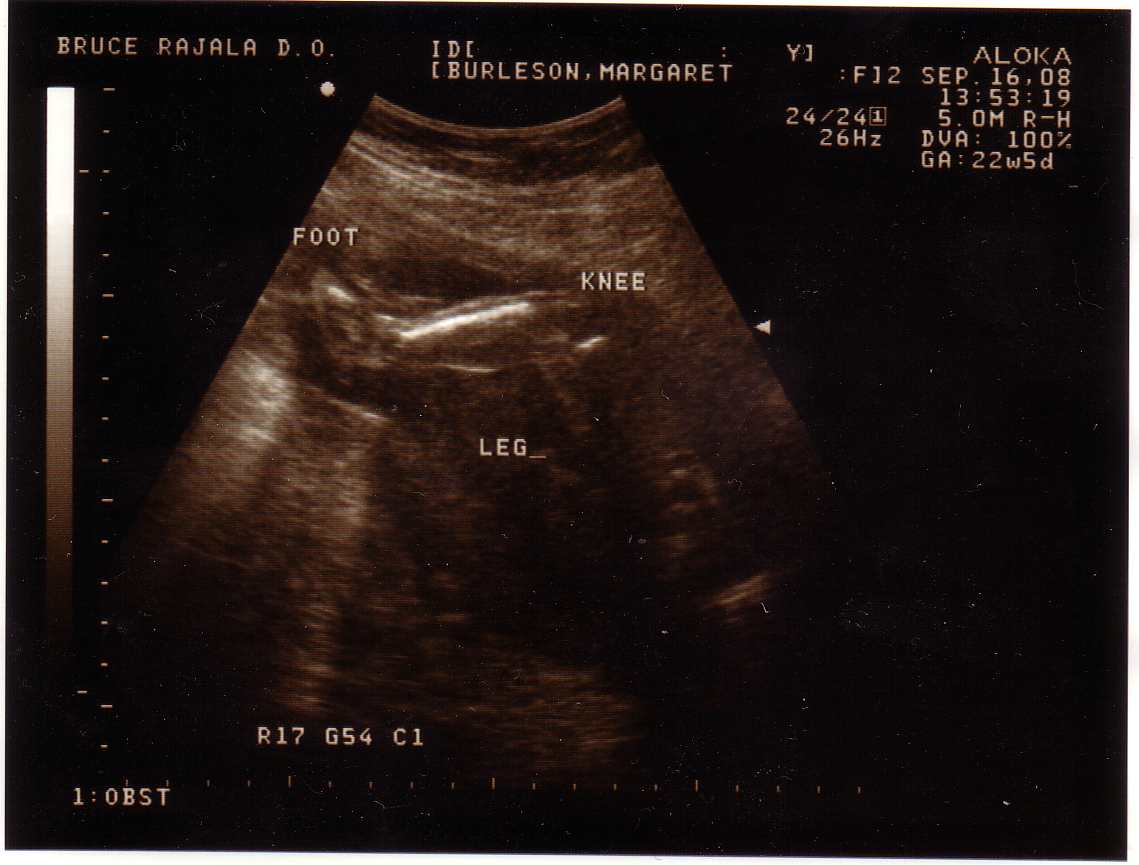

Yesterday was my ultrasound. Patrick worked from home in the morning and then took the rest of the day off to go with Brenden and I to the doctor.

We had the same tech that did my sonogram when I was pregnant with Brenden and I really like her. She is very friendly and patient with all our questions. We were both wavering a little on the way there about finding out the sex of the baby and the tech told us she was the perfect person to talk us back into not knowing, which she did.

Because of Brenden’s hand, my doctor had asked to have special attention paid to the upper limbs. The baby was very cooperative. It clearly flashed us all 10 finger and all 10 toes. The tech said it is very rare to see all the fingers stretched out and we got to see it. Patrick thought it was interesting that the hand the baby showed most closely was the right one (the one Brenden is missing). We also got to see both hands at the same time which is supposed to be rare too.

The baby seemed to want to show us everything we needed to see and nicely kept the legs crossed so we saw nothing we didn’t! So yet again, even if we’d wanted to know the gender, we wouldn’t! Looks like growth is fine and all the chambers of the heart are there. Brain looks good too.

Here are the picts: